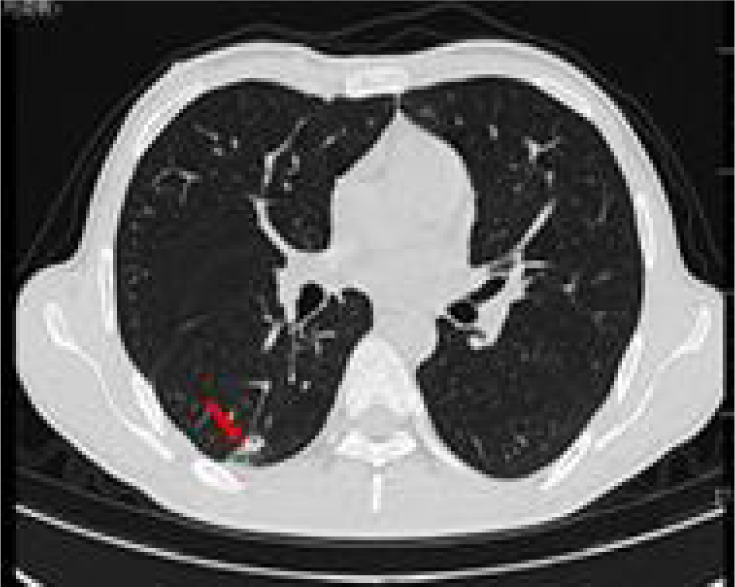

Full abdominal CT and lung CT revealed a high-risk pulmonary nodule in the right lower lobe (Figure 4), pancreatic enlargement with multiple cystic lesions, and multiple ill-defined low-density lesions in both kidneys (Figure 5).

Figure 4: Lung CAT (CT) shows a ground glass nodule (12×9 mm) in the posterior basal segment of the right lower lobe (IM51), with signs of pleural depression (red arrow).

Further examinations were conducted upon admission (Table 1). A chest CAT (CT) scan conducted on January 15, 2021 suggested a possible pulmonary infection with a shadow measuring approximately 19×9 mm in the right lower lobe (Figure 1).

Figure 1: Lung CT shows that there is a calabash type density increase in the dorsal segment of the lower lobe of the right lung, the size of which was about 19×9 mm (red arrow).